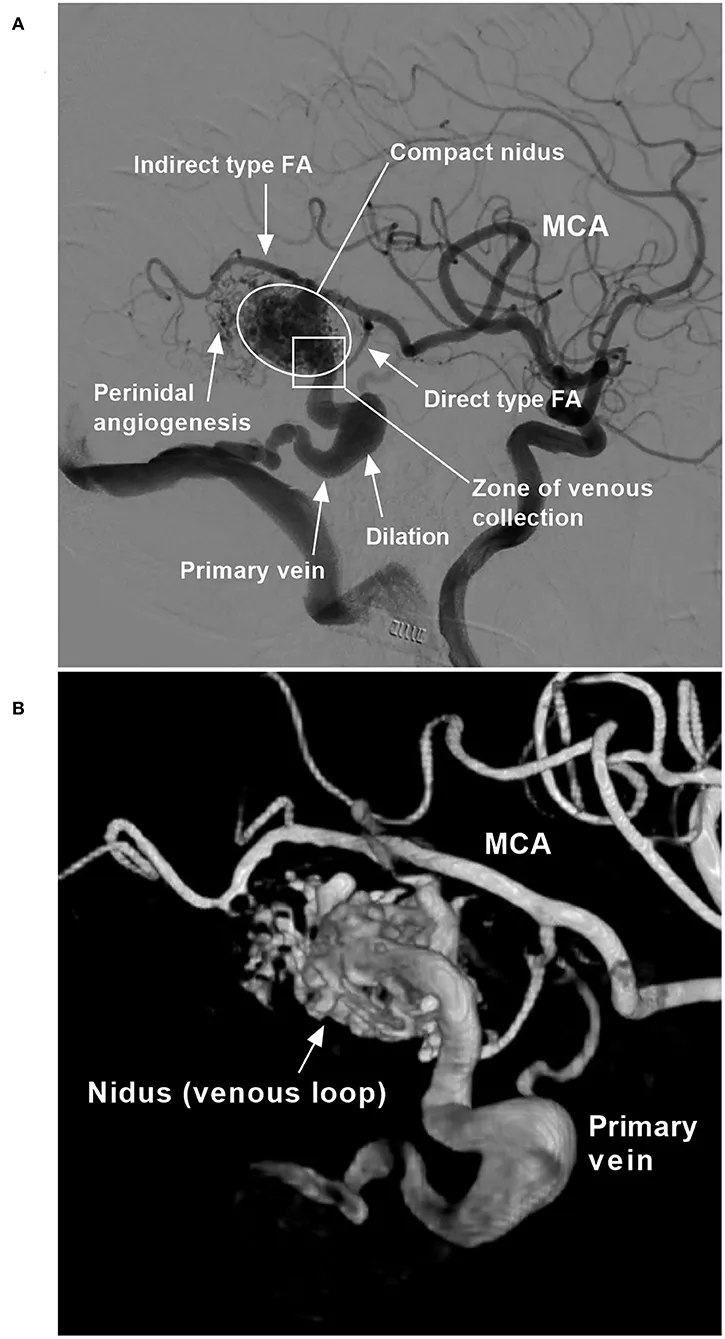

An Arteriovenous Malformation (AVM) is a congenital tangle of vessels where arteries connect directly to veins, bypassing the capillary bed. This creates a high-flow, high-pressure central nidus, prone to rupture and cause intracranial hemorrhage (ICH).

- Gold Standard: Digital Subtraction Angiography (DSA) provides definitive diagnosis and is essential for treatment planning.